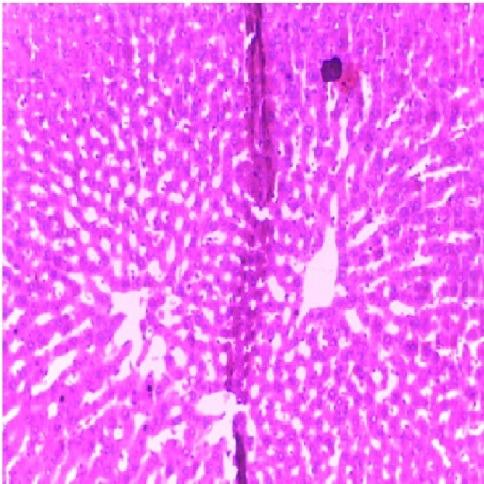

The therapeutic benefit derived from the clinical use of tramadol (TD) has been characterized by hepatotoxicity due to misuse and abuse. The implications of drug-induced hepatotoxicity include socio-economic burden which makes the search for remedy highly imperative. The present study investigated the protective effects of melatonin (MT) and n-acetylcysteine (NAC) on TD-induced hepatotoxicity in albino rats. Forty five adult rats used for this study were divided into nine groups of five rats each. The rats were pretreated with 10mg/kg/day of NAC, 10mg/kg/day of MT and combined doses of NAC and MT prior to the administration of 15 mg/kg/day of TD intraperitoneally for 7 days respectively. At the termination of drug administration, rats were weighed, sacrificed, and serum was extracted and evaluated for liver function parameters. The liver was harvested, weighed and evaluated for oxidative stress indices and liver enzymes. Alanine aminotransferase, alkaline phosphatase, aspartate aminotransferase, total bilirubin, conjugated bilirubin, and malondialdehyde levels were significantly (P<0.05) increased in rats administered with TD when compared to control. Furthermore, glutathione, superoxide dismutase and catalase levels were decreased significantly (P<0.05) in rats administered with TD when compared to control. The Liver of TD-treated rats showed necrosis of hepatocytes. However, the observed biochemical and liver histological alterations in TD-treated rats were attenuated in NAC and MT pretreated rats. Interestingly, pretreatment with combined doses of NAC and MT produced significant (P<0.05) effects on all evaluated parameters in comparison to their individual doses. Based on the findings in this study, melatonin and n- acetylcysteine could be used clinically as remedies for tramadol associated hepatotoxity.

曲马多(TD)临床使用所带来的治疗益处因误用和滥用而表现为肝毒性。药物性肝毒性的影响包括社会经济负担,这使得寻找补救措施迫在眉睫。本研究调查了褪黑素(MT)和N-乙酰半胱氨酸(NAC)对TD诱导的白化大鼠肝毒性的保护作用。本研究使用的45只成年大鼠分为9组,每组5只。在分别腹腔注射15mg/kg/天的TD共7天之前,大鼠分别用10mg/kg/天的NAC、10mg/kg/天的MT以及NAC和MT的联合剂量进行预处理。在药物给药结束时,对大鼠称重、处死,提取血清并评估肝功能参数。摘取肝脏,称重并评估氧化应激指标和肝酶。与对照组相比,给予TD的大鼠丙氨酸氨基转移酶、碱性磷酸酶、天冬氨酸氨基转移酶、总胆红素、结合胆红素和丙二醛水平显著(P<0.05)升高。此外,与对照组相比,给予TD的大鼠谷胱甘肽、超氧化物歧化酶和过氧化氢酶水平显著(P<0.05)降低。TD处理大鼠的肝脏显示肝细胞坏死。然而,在NAC和MT预处理的大鼠中,TD处理大鼠中观察到的生化和肝脏组织学改变有所减轻。有趣的是,与它们的单独剂量相比,NAC和MT联合剂量预处理对所有评估参数均产生显著(P<0.05)影响。基于本研究的结果,褪黑素和N-乙酰半胱氨酸可在临床上用作曲马多相关肝毒性的补救措施。